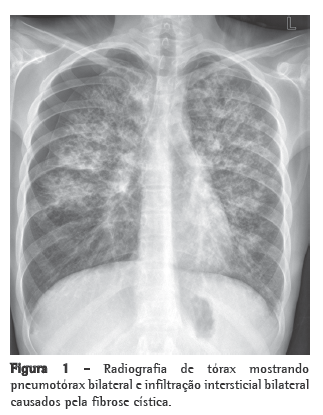

A radiografia de tórax evidenciou abaulamento de arco médio; a tomografia de tórax evidenciou dilatação de ramos arteriais, com relação artéria: brônquio > 1, espessamento septal e micronódulos difusos (Figura 1). A avaliação funcional pulmonar não mostrou alteração de volumes ou fluxos pulmonares, mas evidenciou redução significativa da capacidade de difusão (30% do previsto). Ao ecocardiograma, constatou-se aumento de câmaras direitas e pressão sistólica de artéria pulmonar estimada em 84 mmHg. No teste de caminhada de seis minutos (TC6), a distância percorrida foi de 375 m. As investigações para doenças do tecido conectivo, AIDS, hipertensão portal e embolia pulmonar crônica tiveram resultados negativos.